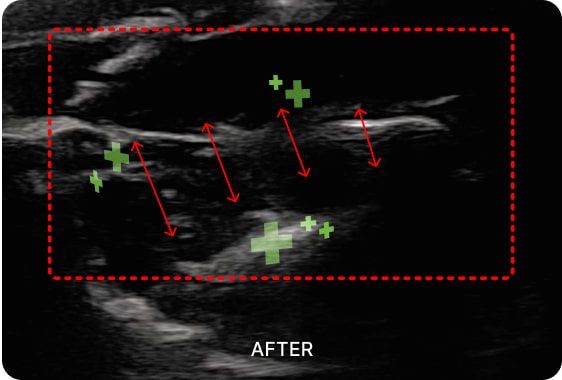

초음파 유도 시술을 통해

턱관절 장애 통증을 유발하는

심부 근육을 치료할 수 있습니다.

01. PDRN 약침

PDRN 약침은 인체의 DNA와 90% 이상 유사한 구조로 세포 증식을 활성화하여

손상된 조직을 복구하는 효과가 뛰어납니다. 초음파를 활용하여 신경을 압박하는

염증을 박리하고 손상된 조직을 재생합니다.